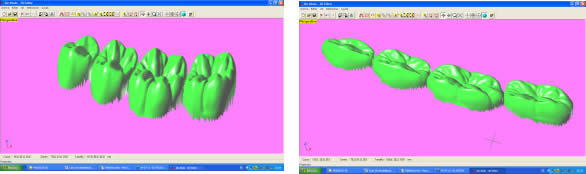

Introducción.- En oclusión, existen varios campos de aplicación básica para la digitalización. Hablamos, preferentemente, de la digitali- zación tridimensional. Recordemos que esta palabra es sinónimo de medición y –como tal- auxilio en esta rama odontológica tan necesitada de precisión. La digitalización tridimensional consistirá en el registro de la posición espacial, de un finito número de puntos, determinando sus coordenadas -x,y,z-. A menor distancia entre cada punto se conseguirá como resultado un objeto virtual con mayor detalle, coincidente con el real. Con cada triada se podrá formar una superficie, que continuada con la generada por el resto de la malla de puntos, completarán la forma del objeto. Este es el origen de donde partimos para establecer el concepto básico de las revolucionarias aplicaciones 3D. Se parte así del denominado escaneado tridimensional: Escaneado Superficial de un objeto real -> “Nube de Puntos” -> “Malla de Alambre” -> Superficie del Objeto Virtual. Con los modelos dentarios, impresiones o registros de oclusión, virtuales (en la pantalla del ordenador), realizaremos ahora, mediante un programa informático, la manipulación simulada, mediante computadora, para la realización del estudio y diseño de la oclusión. La Oclusión Computarizada (OC) –dentro de la más amplia Odontología Computarizada- comprende, hoy, fundamentalmente, tres fines: 1º)- El Estudio, Diagnóstico y Plan de Tratamiento Asistidos por Ordenador. 2º)- El Encerado Computarizado. (Por RP –Rapid Prototyping-, Prototipado Rápido, o por CAM –Computer Assisted or Aided Machining or Manufacturing-, Maquinado Asistido o Ayudado por Computador). 3º)- La Restauración y Confección de Prótesis Computarizada. (Por CAD-CAM, -Computer Assisted Design – Computer Assisted Manufacturing-, Diseño y Fabricación Asistidas por Computador). La Odontología Computarizada tiene entre sus numerosas secciones, ésta de oclusión, considerada primordial en el trabajo clínico habitual, desde la que nos relacionamos con la ortodoncia, cirugía implantológica, tecnología protésica y prostodoncia. Cada uno de los citados fines de la OC necesita partir de un escaneado tridimensional de los objetos a tratar: elementos del sistema dentario (arcadas) –de forma directa, en la misma boca del paciente-, o modelos dentales obtenidos por una impresión material de éstas y su posterior escaneado –o forma indirecta, fuera de la boca del paciente-. El escaneado se puede realizar con variados dispositivos, resultando procedimientos de distintos tipos y con diferentes características, clasificados simplificadamente como: A) Escaneado de contacto, háptico: B) Escaneado sin contacto: Tomando una imagen del objeto, marcado por líneas o cuadrículas luminosas proyectadas sobre su superficie, que se deforman con ella, analizándose luego digitalmente. El escaner se considera aquí un analizador trigonométrico del objeto, que registra su imagen, marcada mediante un rayado por luz –normalmente láser- (que permite, mediante software, obtener las coordenadas espaciales de multitud de puntos, que son agrupados en unidades de tres, constituyendo los vértices de una superficie triangular, que sumándose a las vecinas, llegarán a representar la envuelta completa del objeto y así su forma volumétrica o tridimensional). C) Combinado. Externo e Interno. Los escáneres suelen resultar, actualmente, poco económicos, y aunque van decreciendo en coste, están –para estas fechas- en un nivel que suele partir como mínimo de los 8.000 euros; siempre dependiendo del procedimiento de registro empleado, tamaño y precisión del escaneado. Existen: A) aparatos integrados en sistemas dentales, desarrollados específicamente para nuestro campo, de comprobada eficacia y de alto coste económico; B) dispositivos de uso general, aplicables a los propósitos de la odontología, de complicada adaptación pero de muy bajo coste relativo; C) múltiples posibilidades para la construcción de un escaner propio, casero y económico, que pueda, con suficiente experiencia, llegar a funcionar para uso profesional, gracias a la existencia de suficiente información de la tecnología empleada, ampliamente divulgada y de fácil desarrollo; útiles para fines diagnósticos. En oclusión necesitamos el 3D, pero también el 4D. Sumamos aquí a las tres coordenadas espaciales de cada punto del objeto, otra más, la cuarta dimensión: el tiempo. Dado que un objeto móvil, lo es por la temporalidad de sus posiciones en el espacio. Así se registrarán y analizarán digitalmente los movimientos mandibulares para conseguir la articulación y reproducción de la función masticatoria. Para esto se han aplicado determinados registros, mediante sensores de posición o por receptores de actividad muscular, como los electromiógrafos, o el más específico articulador virtual, del que se encuentran diferentes productos de software, englobados –como complemento necesario- en los programas que acompañan a los distintos sistemas de cad-cam dental. Desde el escaneado, o transformación u obtención del objeto real en cuerpo 3D, numérico, adquirido para ser estudiado y manipulado de forma digital, virtual, en el computador, continuamos con otras vías, ahora posibles, de enorme potencial, desde el estudio y planificación a la fabricación protésica. Así van a ser expuestas a continuación: A) La planificación; B) el encerado; y C) la fabricación. A) -Estudio, Diagnóstico y Plan de Tratamiento Asistidos por Ordenador. La planificación de la rehabilitación oclusal, puede iniciarse: A-1) Por Registro Estático Morfológico Computarizado, del aparato estomatognático y sistema dentario. Que puede realizarse: I) A partir de Escaneado Extraoral. I-a) Escaneado Volumétrico (CT–tomografía computarizada-) (O mejor, CBCT –tomografía computarizada de haz cónico-, de menor radiación y coste, con aparatos diseñados específicamente para uso dento-máxilo-facial ). I-b) Escaneado Superficial –de los modelos de estudio- y Registros Oclusales-. II) A partir de Escaneado Intraoral. II-a) Escaneado Volumétrico (CT local, o CBCT local, que se están desarrollando para aplicación retroalveolar). II-b) Escaneado Superficial –de las caras oclusales del sistema dentario-. A-2) Por Registro (Estático Morfológico Computarizado) de Huellas de Oclusión (o Registros Oclusales), para análisis de contactos intermaxilares, estáticos -y menos o indirectamente los movimientos mandibulares-. Mediante escaneado superficial de registros, sus modelos 3D, y combinación o no, con el Papel de Articular Electrónico (T-Scan). A-3) Por Registro Dinámico Funcional (fisiológico) Computarizado: I) Registro Computarizado (Integrado) de los Movimientos Mandibulares –electropantográfico o cinematográfico-. Por sensores o marcadores de posición. II) Registro Computarizado (Integrado) de la Función Muscular –electromiográfico-. A-4) Por Integración Informática de varios de los Registros citados. B) -Encerado Computarizado. Es el modelado o diseño virtual en la pantalla del ordenador y su realización en material de patronaje (como la cera u otro de similar; económico, modificable, transformable y rápido), que puede realizarse por: B-1) Por RP –prototipado aditivo- o B-2) por CAM –maquinado sustractivo-. Como pensamos en el concepto clásico, la realización de un encerado diagnóstico es clave para una rehabilitación oclusal correcta. Además el encerado servirá para la confección de: a) una posible férula radiológica y quirúrgica, b) una referencia para el tallado, la prótesis o rehabilitación temporal y el patrón para la definitiva. Se llevará a cabo, en dos etapas: 1ª) Etapa de creación del patrón. Elaboración virtual en la pantalla del ordenador. Necesitando el software apropiado, CAD. 2ª) Etapa de confección. Elaboración Real, mediante RP o CAM. 1ª) La etapa de creación virtual del patrón en la pantalla del ordenador, mediante un programa informático de diseño y manejo de objetos tridimensionales, (siempre partiendo de un registro previo, como el escaneado de los modelos), puede facilitarse con varias herramientas para: -Elaboración Virtual por Adición. 2ª) La etapa de confección, o elaboración real, mediante RP o CAM. -Confección por RP (Rapid Prototyping) –Prototipado Rápido-, de adición o construcción capa a capa, añadiendo una sustancia que se endurece, aumentando su nivel en superficie. La elaboración real por adición, es posible en un variado –pero limitado- tipo de materiales. -Confección por CAM (Computer Aided Machining) –Maquinado o Tallado Asistido por Ordenador-, de eliminación de sustancia o esculpido en un bloque sólido. La elaboración real por sustracción, es posible en un numeroso -y casi ilimitado- tipo de materiales. Existen gran cantidad de dispositivos que consiguen la fabricación y consecución física de un encerado real, a partir de su elaboración virtual, desde un escaneado y su diseño computarizado. Todos los sistemas denominados de cad-cam dental, en general, aunque no estén espe- cialmente dispuestos para ello, pueden dedicarse a este propósito; simplemente colocando un material de patronaje, como la cera, en lugar del material con el que se constituirá la prótesis definitiva. Pero, existen –también- sistemas espe- cialmente configurados para el trabajo en material de diseño, normalmente: ceras, resinas o compuestos, es lo que se denomina prototipado rápido (rapid prototyping). En la industria general, la fabricación de cualquier objeto en serie, requiere de estos procedimientos en las primeras etapas de elaboración para su producción. La más económica y reducida Impresora 3D o Sistema de Prototipado Rápido, que puede confeccionarnos unos maxilares, a partir de la tomografía, o un encerado diagnóstico, según el software disponible. Su precio actual 45.000 Euros. C) -Restauración y Confección de Prótesis Computarizada. (Por CAD-CAM). Es el modelado o diseño virtual en la pantalla del ordenador y su realización en material definitivo (como porcelana, titanio, aleación preciosa, u otro similar); poco económico, difícilmente o no modificable, ni transformable y que requiere de un tiempo adecuado, mucho mayor que el requerido para la confección del patrón de material plástico. Esto puede realizarse por numerosos dispositivos. Existen gran variedad de sistemas para el diseño y confección de restauraciones y prótesis. Son los denominados gene- ralmente SISTEMAS DE CAD-CAM DEN- TAL (Dental Cad-Cam System): (Entre estos sistemas encontramos los que también pueden planificar el tratamiento restaurativo y realizar el encerado diagnóstico con diseño y confección de un patrón oclusal; como hemos referido antes). Históricamente estos sistemas comenzaron con la década de los setenta -en 1971, con el Holodontography-Altschuler System-, y con el Sopha System de Duret, progresando enormemente hasta comienzos de los noventa. Durante esos veinte años, se potenció su desarrollo con el siguiente hito histórico que los encumbró, en su segunda década, por la aparición de los principales impulsores del cad-cam clínico comercializable -Mörmann y Brandestini, en 1981-, denominado Sistema Cerec. También se establecieron los principios de estos dispositivos con el DCS Dental System, el CAP System, el Minnesota-Rekow System, el Nissan Cad/Cam System, Automill y Microdenta System. El culmen del progreso se alcanzó a mediados de los noventa, con sistemas ampliamente comercializados y evolucionados hasta hoy: Procera, DCS Dental, o Cicero. En los siguientes diez años, se continuó perfeccionando los sistemas citados; hubo algunos sistemas no comerciales o de escasa difusión, o distribuidos moderadamente; repre- sentando un período hasta el 2000, con una pequeña depresión, en los años medios, por el declive en la extensión de estos productos, en relación al extraordinario futuro que se les auguraba, motivada por el alto coste de los equipos y las limitaciones en su potencia digital, en el que –aún y así- aparecieron sistemas como: Belledent, Cadim, Dentscan, CCD System, Cynovad, Digident-Girrbach, Decim y Etkon. La segunda revolución para la odontología por cad-cam se produjo con el comienzo del siglo. Ampliándose enormemente la cantidad de sistemas y alentándose una explosión del trabajo digital en odontología, con: Cercon-Degussa, Lava-3M-Espe, Cad-Esthetics System-Ivoclar, DDS, GC-Dental, Everest-Kavo y Bego. En estos momentos el futuro de la odontología se encuentra inexorablemente unido a estos aparatos. Para el clínico o el laboratorio dental es hoy imprescindible contar con ellos. Siguen nuevas apariciones, como el sistema Hint-Els, o el Evolution-4D, similar al Cerec, que fue el pionero, pero que todavía, a la fecha, se mantiene como el más versátil, modulable y práctico, con progresos como el facilitado trabajo de diseño tridimensional o el nuevo escaneado extraoral independiente. Los sistemas de cad-cam, están integrados por: un escaner que digitaliza el objeto dental, un ordenador con el software adecuado para el diseño virtual, y una máquina de tallado para la fabricación del objeto diseñado en un material determinado. Una relación actualizada, de gran número de los sistemas existentes se encuentra en “Aktuelle CAD/CAM Systeme”, en http://www.tu-dresden.de/medprothetik/computerzahn/CAD-CAM-Systeme.htm Factores clave en la Oclusión Computarizada-. La digitalización del estudio, diagnóstico y tratamiento de la oclusión, como la construcción o restauración de un sistema dentario óptimo para la correcta función masticatoria del aparato estomatognático, pretende facilitar y generalizar la excelencia en el trabajo clínico. Es una aplicación de preferencia informática porque pueden manejarse gran cantidad de datos, mediciones, relaciones geométricas, unidas a la tridimensionalidad y la movilidad de sus elementos, de una forma racional, lógica y científicamente fundamentada, aún partiendo de concepciones filosóficas o criterios sujetos a distintas escuelas de oclusodoncia. La digitalización de la oclusión pude llevar- nos a despejar supuestos sin evidencia científica, de la que adolece sectorialmente nuestro arte. Tenemos suficientes fórmulas, reglas y relaciones numéricas, aportadas por numerosos autores, que tienen que se recopiladas y que pueden así ser aplicadas. Yá que la digitalización recoge todos los datos métricos y posicionales (coordenadas de cada punto, con su x,y,z), del sistema dentario, se pueden establecer fórmulas matemáticas para que -siendo la z la determinante de la altura de un punto en el espacio-: una z máxima, de una pieza mandibular, esté más o menos próxima a una z mínima de una pieza maxilar; que un punto (de cúspide) -con una determinada x,y- maxilar, coincida con otro –con la misma x,y- mandibular, pero con distintas aunque casi idénticas z, dándose el contacto oclusal. Y de esta forma, con sucesivas relaciones (matemáticas) se construiría una oclusión tendente a la excelencia; matemáticamente desarrollada. Así podría confeccionarse, automáticamente, una oclusión geométrica, dando, por ejemplo, solamente: la posición base de cada pieza, la x,y de las cúspides de una hemiarcada, y la altura de su plano oclusal, y automáticamente se generarían las cúspides agonistas y antagonistas, y la morfología dental completa de ambas arcadas. Se tendrían que añadir los datos correspondientes a los dientes anteriores, a las ATMs y las fórmulas de relación de las pendientes. Distintos autores han desarrollado relaciones métricas en oclusión. Algunos han simplificado el proceso, como partida, para ir añadiendo variantes; así, pueden usarse valores standard, normales, del ángulo cuspídeo para fabricar la morfología oclusal en CAD/CAM, -cuando la creación del esquema oclusal es de novo-, según Hobo y Takayama; y el uso de varios valores fijos de partida, universalmente aceptados, en lugar de la medida directa de la pendiente condilar es, según los mismos autores, muy importante en el desarrollo extenso de los sistemas de CAD/CAM. Así, el procedimiento de «twin-stage» propuesto por estos autores, en su libro “Oral Rehabilitation”, proporciona una solución en la producción de una oclusión dinámica tridimensional para el CAD/CAM. Otra técnica, consiste en el encerado virtual, mediante un modelado CAM, siguiendo las etapas de Shillimburg, o Kuwata, elaborando paso a paso la morfología oclusal, orientada a su enfrentamiento con el antagonista, encaminando los volúmenes cuspídeos como en el encerado progresivo clásico, gota a gota. Se realizaría su construcción virtual en la pantalla del ordenador, pudiendo estar facilitada su manipulación, mediante “espátulas de encerado virtual”, utilizando los digitalizadores de brazo articulado, con los que se pueden disponer los volúmenes necesarios, en la posición espacial que se desee. No obstante, el modelado dental se puede realizar siempre, aunque sea a través del clásico ratón del ordenador, de forma virtual, con la imagen tridimensional en la pantalla, utilizando diferentes procedimientos, con el software adecuado: A) Automático, a partir de las reglas dentométricas, odontométricas y cefalométricas, relacionadas con la gnatología, tomando previamente los valores claves necesarios del paciente. B) Mediante diseño de la anatomía con trazado de los perfiles, líneas y curvas, que van a definir las superficies dentales. Trabajando bidimensionalmente, en base a cortes de la estructura a construir, que manipulada variando sus dos dimensiones, va a corresponderse con la morfología dental tridimensional, al establecerse un área de influencia y cambio en los cortes vecinos, y así alterándose el volumen dental completo. Este era el procedimiento de variación anatómica utilizado, durante dos décadas con el Sistema Cerec (el Cerec 1, Cerec 2 y Cerec 3), hasta la llegada del Cerec 3D. C) Mediante copiado de la cara oclusal ideal, realizada previamente en cera u otro material real, del diente, su registro oclusal o su antagonista, en el concepto original del Sistema CEREC, de construcción oclusal mediante Correlación –copiando un encerado previo- o Función –correspondiendo automáticamente a la cara oclusal del antagonista-. D) Mediante selección de dientes, individuales o en grupo (incisivos, caninos, premolares, molares, arcadas, hemiarcadas, sistema dentario, maxilares o mandibulares), de entre un grupo de archivos de modelos dentales tridimensionales virtuales, como una librería de objetos 3D. Como en la selección de las tablillas de dientes para la confección de las prótesis completas. Escogiendo tamaño y forma. Colocando cada pieza o bloque en su lugar, con la disposición espacial y oclusal correspondiente. E) Mediante la misma selección, antes citada, seguida luego de una transformación, como estiramiento o estrechamiento, u otras variaciones morfológicas, con las herramientas de edición del programa informático, hasta conseguir la oclusión que se pretende. F) Mediante encerado virtual, de adición progresiva de volúmenes anatómicos, en el concepto clásico de encerado gota a gota, con la metódica de P. K. Thomas, para restauraciones parciales, o de Kuwata, para rehabilitaciones extensas. El método de encerado es el que nos permitirá la construcción de una oclusión individualizada. Pero la necesidad de utilización de un articulador es evidente. Es presumible que se desarrollen nuevos instrumentos para la perfección de la oclusión computarizada, semejantes a los articuladores mecánicos tradicionales. Serán los denominados articuladores virtuales, (VA –Virtual Articulator-), o simuladores digitales de la articulación oclusal, consistentes en un programa informático, capaz de relacionar los modelos virtuales, permitiendo movimientos similares a los naturales del paciente: es la aplicación de la tecnología de la realidad virtual a la oclusión (VR –Virtual Reality-). Esto es lo que nos permitirá pasar de la fórmula empleada generalmente para el modelado oclusal, que suele ser estática y referida a un registro de las superficies antagonistas, a un sistema experto que reproduzca la relación completa de ambas arcadas, las articulaciones, y su combinación con los movimientos masticatorios: realizando la dinámica mandibular. Hoy en la mayoría de los sistemas de cad-cam, los trabajos oclusales se realizan, extensamente, basados sólo en el enfrentamiento con el antagonista, sin tener en cuenta la movilidad mandibular, las guias condilares o anteriores. Es como si realizásemos un encerado oclusal sin tener en cuenta los determinantes anteriores y posteriores, y trabajásemos en un articulador, no ajustable, o simplemente en un Oclusor o Verticulator, sin giro de cierre ni desplazamientos horizontales.El articulador virtual, por software, para el diseño oclusal en la pantalla del ordenador, aún no es empleado de forma generalizada en estos sistemas, pero ya se encuentran como aplicaciones en algunos de ellos. Uno de los pioneros se utiliza en el sistema Cynovad. Aquí, directamente relacionado con la confección de un encerado oclusal. Otros dispositivos electrónicos y digitales, de registro por ordenador, que podrían combinarse con la construcción plástica de la oclusión, en cera u otro material, solo se están utilizando para diagnóstico, o como complementos a articuladores mecánicos sofisticados; así podemos encontrar programas como Rosy32 Robot System (Diagnostic Articulator), de registro dinámico, el VirtSet, de diagnóstico y predicción oclusal-ortodóntica, o el ArtiKulator-Software (ver ArtiDemo), de programación virtual de un articulador, con elección del equivalente mecánico real (Sam, Artex, Kavo,…). Entre éstos, el sistema más completo desarrollado, con escaneado de modelos y registros, y correspondencia con la dinámica mandibular, obtenida por un arco facial cinemático, con sensores de posición y movimiento, es el DentCAM.Para clasificar los instrumentos de oclusión, consideramos muy completa la clasificación de los articuladores mecánicos, desarrollada en The International Workshop Occlusion, de 1972, University of Michigan: 1) Clase I – Sujetadores simples de modelos. Subdivisión A (Con movimientos verticales; Corelator, Verticulator). Subdiv. B (Con articulación de bisagra sin desplazamientos horizontales; Centric Relator). Conclusiones (parciales para esta primera parte).- El articulador virtual podría establecerse a partir del escaneado de un articulador mecánico seleccionado, a partir de un modelo construido íntegramente por CAD de forma virtual, o –idealmente- a partir de un patrón anatómico, individual, a partir de la radiología tridimensional (como la Tomografía Computarizada). A estas estructuras se les sumarán los datos necesarios para la función: relación intermaxilar –estática- (oclusal) y relación cráneo-mandibular dinámica (pendiente condílea y Bennett), con ayuda también del registro de la actividad muscular (electromiografía). A la clasificación de los articuladores antes expuesta, le podemos añadir ahora el Tipo V, constituido por los Articuladores Virtuales, o instrumentos informáticos que pueden reproducir la oclusión dental en el ámbito de la realidad virtual, que se desarrollan como programas informáticos concretos, de muy variada composición en sus elementos de software, y distintos por los diferentes tipos de registros que necesitan para su efectiva y precisa actuación. Dentro de este V grupo, a su vez, podríamos –paralelamente a la clasificación de los articuladores mecánicos-, establecer tantas subclases como las de los tipos y subclases de aquellos. Así habría de clase I, como ocurre mayoritariamente en los sistemas de Cad-Cam dental actuales, cuando utilizamos modelos dentales 3D y registros estáticos de antagonistas. Es éste el cambio que se experimentará en los próximos años, en la Oclusión Computarizada: la utilización generalizada de Articuladores Virtuales de clase III y IV. Bibliografía Cooper BC. Parameters of an optimal physiological state of the masticatory system: the results of a survey of practitioners using computerized measurement devices. Cranio. 2004 Jul;22(3):220-33. Reiss B. Occlusal surface design with Cerec 3D. Int J Comput Dent. 2003 Oct;6(4):333-42 Petrie CS, Woolsey GD, Williams K. Comparison of recordings obtained with computerized axiography and mechanical pantography at 2 time intervals. J Prosthodont. 2003 Jun;12(2):102-10. Kojima T, Sohmura T, Nagao M, Wakabayashi K, Nakamura T, Takahashi J. A preliminary report on a computer-assisted dental cast analysis system used for the prosthodontic treatment. J Oral Rehabil. 2003 May;30(5):526-31 Bernhardt O, Kuppers N, Rosin M, Meyer G. Comparative tests of arbitrary and kinematic transverse horizontal axis recordings of mandibular movements. J Prosthet Dent. 2003 Feb;89(2):175-9 Tsai HH. A computerized analysis of dental arch morphology in early permanent dentition. ASDC J Dent Child. 2002 Sep-Dec;69(3):259-65, 234 Ferrario VF, Sforza C, Serrao G, Schmitz JH. Three-dimensional assessment of the reliability of a postural face-bow transfer. J Prosthet Dent. 2002 Feb;87(2):210-5. Kerstein RB. Current applications of computerized occlusal analysis in dental medicine. Gen Dent. 2001 Sep-Oct;49(5):521-30 Kerstein RB, Wilkerson DW. Locating the centric relation prematurity with a computerized occlusal analysis system. Compend Contin Educ Dent. 2001 Jun;22(6):525-8, 530, 532 passim; quiz 536. Sohmura T, Kojima T, Wakabayashi K, Takahashi J. Use of an ultrahigh-speed laser scanner for constructing three-dimensional shapes of dentition and occlusion. J Prosthet Dent. 2000 Sep;84(3):345-52. Kerstein RB. Computerized occlusal management of a fixed/detachable implant prosthesis. Pract Periodontics Aesthet Dent. 1999 Nov-Dec;11(9):1093-102 Tarantola GJ. A computerized model for teaching various methods of positioning the condyles to centric relation. Gen Dent. 1999 May-Jun;47(3):308-12 Gsellmann B, Schmid-Schwap M, Piehslinger E, Slavicek R. Lengths of condylar pathways measured with computerized axiography (CADIAX) and occlusal index in patients and volunteers. J Oral Rehabil. 1998 Feb;25(2):146-52 Tamaki K, Celar AG, Beyrer S, Aoki H. Reproduction of excursive tooth contact in an articulator with computerized axiography data. J Prosthet Dent. 1997 Oct;78(4):373-8 Garcia Cartagena A, Gonzalez Sequeros O, Garrido Garcia VC. Analysis of two methods for occlusal contact registration with the T-Scan system. J Oral Rehabil. 1997 Jun;24(6):426-32 Matsui Y, Ohno K, Michi K, Suzuki Y, Yamagata K. A computerized method for evaluating balance of occlusal load. J Oral Rehabil. 1996 Aug;23(8):530-5 Giddon DB, Sconzo R, Kinchen JA, Evans CA. Quantitative comparison of computerized discrete and animated profile preferences. Angle Orthod. 1996;66(6):441-8 Matsui Y, Neukam FW, Wichmann M, Ohno K. A computerized method for evaluating distribution of occlusal load on implant-supported fixed cantilever prostheses. Int J Oral Maxillofac Implants. 1996 Jan-Feb;11(1):67-72 Hayashi T, Saitoh A, Ishioka K, Miyakawa M. A computerized system for analyzing occlusal relations during mandibular movements. Int J Prosthodont. 1994 Mar-Apr;7(2):108-14 Maness WL. Computerized occlusal analysis. J Can Dent Assoc. 1993 Aug;59(8):701-2 Edwards CL, Richards MW, Billy EJ, Neilans LC. Using computerized cephalometrics to analyze the vertical dimension of occlusion. Int J Prosthodont. 1993 Jul-Aug;6(4):371-6 Giannazzo E, Leonardi R, Scivoli M, Rapisardi CB, Vassallo V. [Computerized parametrization in orthognathodontics] Boll Soc Ital Biol Sper. 1993 Jun;69(6):373-9 Harvey WL, Osborne JW, Hatch RA. A preliminary test of the replicability of a computerized occlusal analysis system. J Prosthet Dent. 1992 May;67(5):697-700 Boening KW, Walter MH. Computer-aided evaluation of occlusal load in complete dentures. J Prosthet Dent. 1992 Mar;67(3):339-44 Reza Moini M, Neff PA. Reproducibility of occlusal contacts utilizing a computerized instrument. Quintessence Int. 1991 May;22(5):357-60 Harvey WL, Hatch RA, Osborne JW. Computerized occlusal analysis: an evaluation of the sensors. J Prosthet Dent. 1991 Jan;65(1):89-92 Palano D, Molinari G, Salvo C. [Electromyography and computerized magnetic gnathokinesiography in the diagnosis and therapy of craniomandibular disorders] Minerva Stomatol. 1990 Dec;39(12):977-87